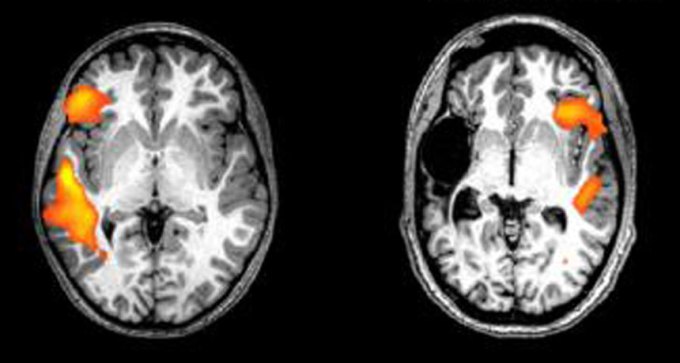

13. Neuroscience

Babies can recover language skills after a left-side stroke

Very young babies who have strokes in the language centers of their brain can recover normal language function — in the other side of their brain.